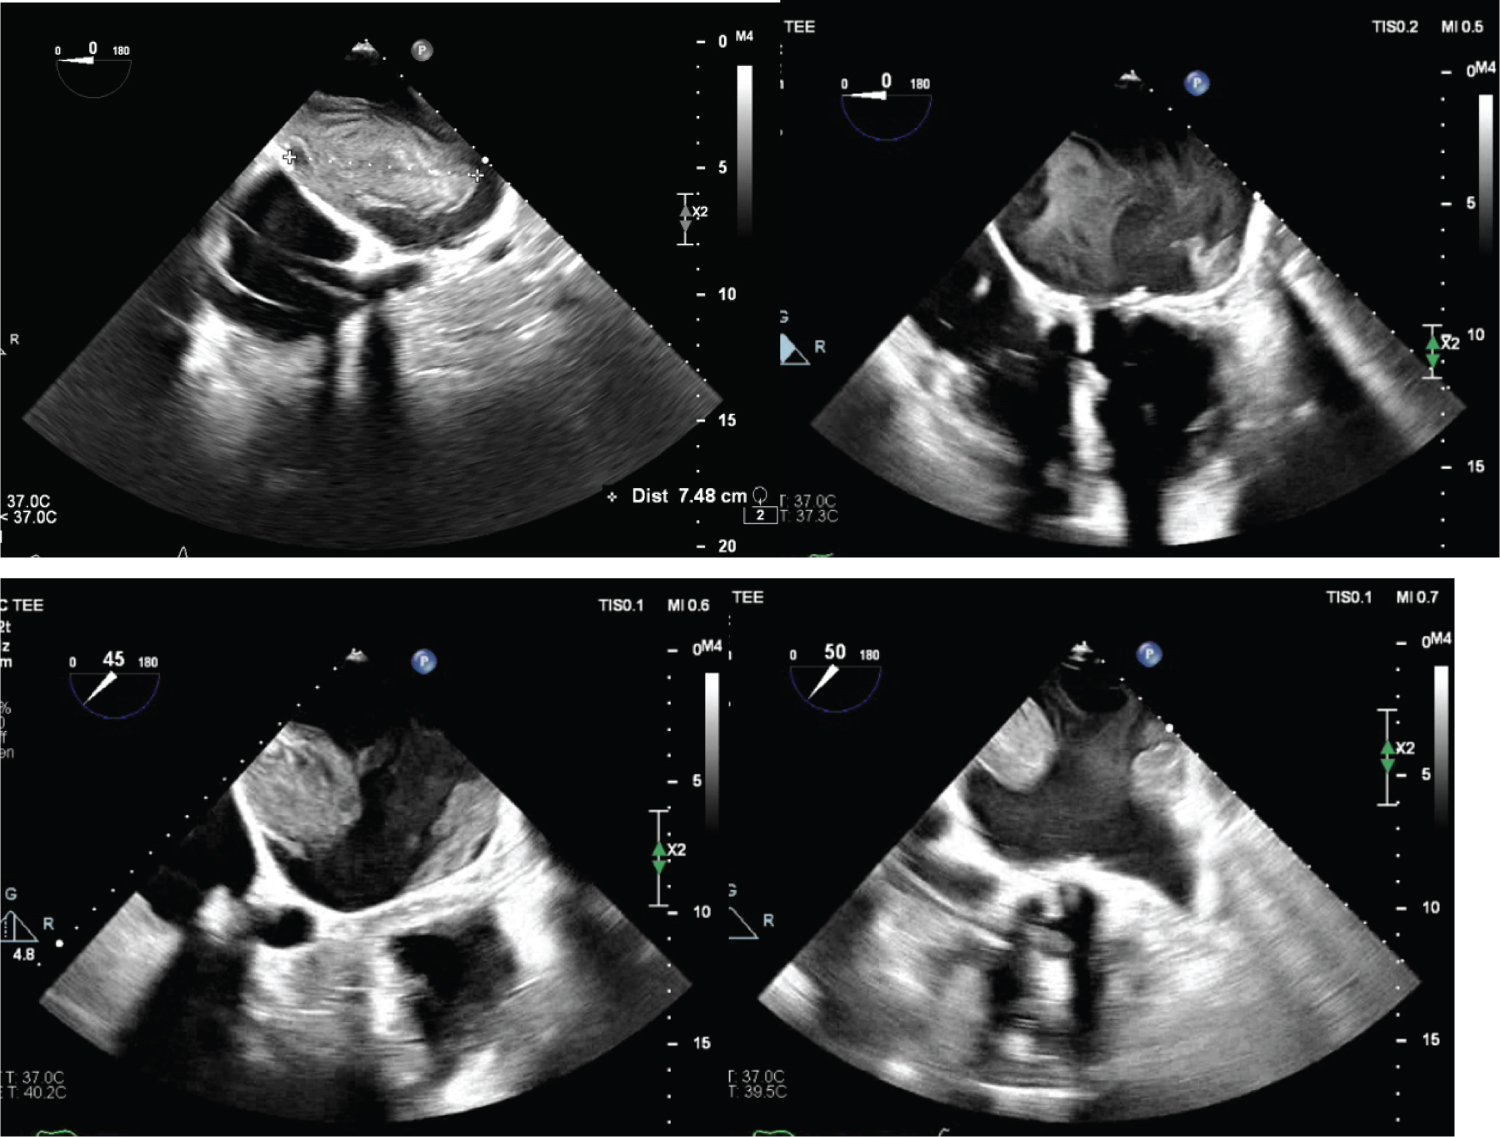

57-year-old female with a history of bioprosthetic mitral valve replacement 6 years prior (27 mm Carpentier Edwards), rate-controlled atrial fibrillation s/p dual-chamber pacemaker on warfarin, and nonischemic cardiomyopathy with reduced ejection fraction of 35%. Patient presented to the hospital for 3 days for worsening shortness of breath. Given concerns of known upper extremity thrombosis, a computerized tomography scan of the chest with contrast was used to rule out a pulmonary embolism and showed an enlarged left atrium with large filling defect. INR on admission was 2.8. On transesophageal echocardiogram (TEE) the next day, there was found to be multiple large left atrial thrombi (largest measuring 7.48 × 3.12 cm), with a significantly dilated left atrium thought to be secondary to a severely stenotic mitral valve. On discussion with the multidisciplinary heart team, we decided to proceed with redo surgical mitral valve replacement and thrombus removal (Figure 1).

Figure 1: Left atrial thrombus seen on transesophageal echocardiogram.

The length of one of the thrombi is measured at 7.48 cm in the left upper image. Two separate thrombi can be seen in the left lower image. Interestingly, the left atrial appendage in the right lower image is without a thrombus. View Figure 1